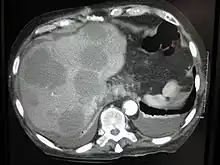

Cut surface of a liver showing multiple paler metastatic nodules originating from pancreatic cancer